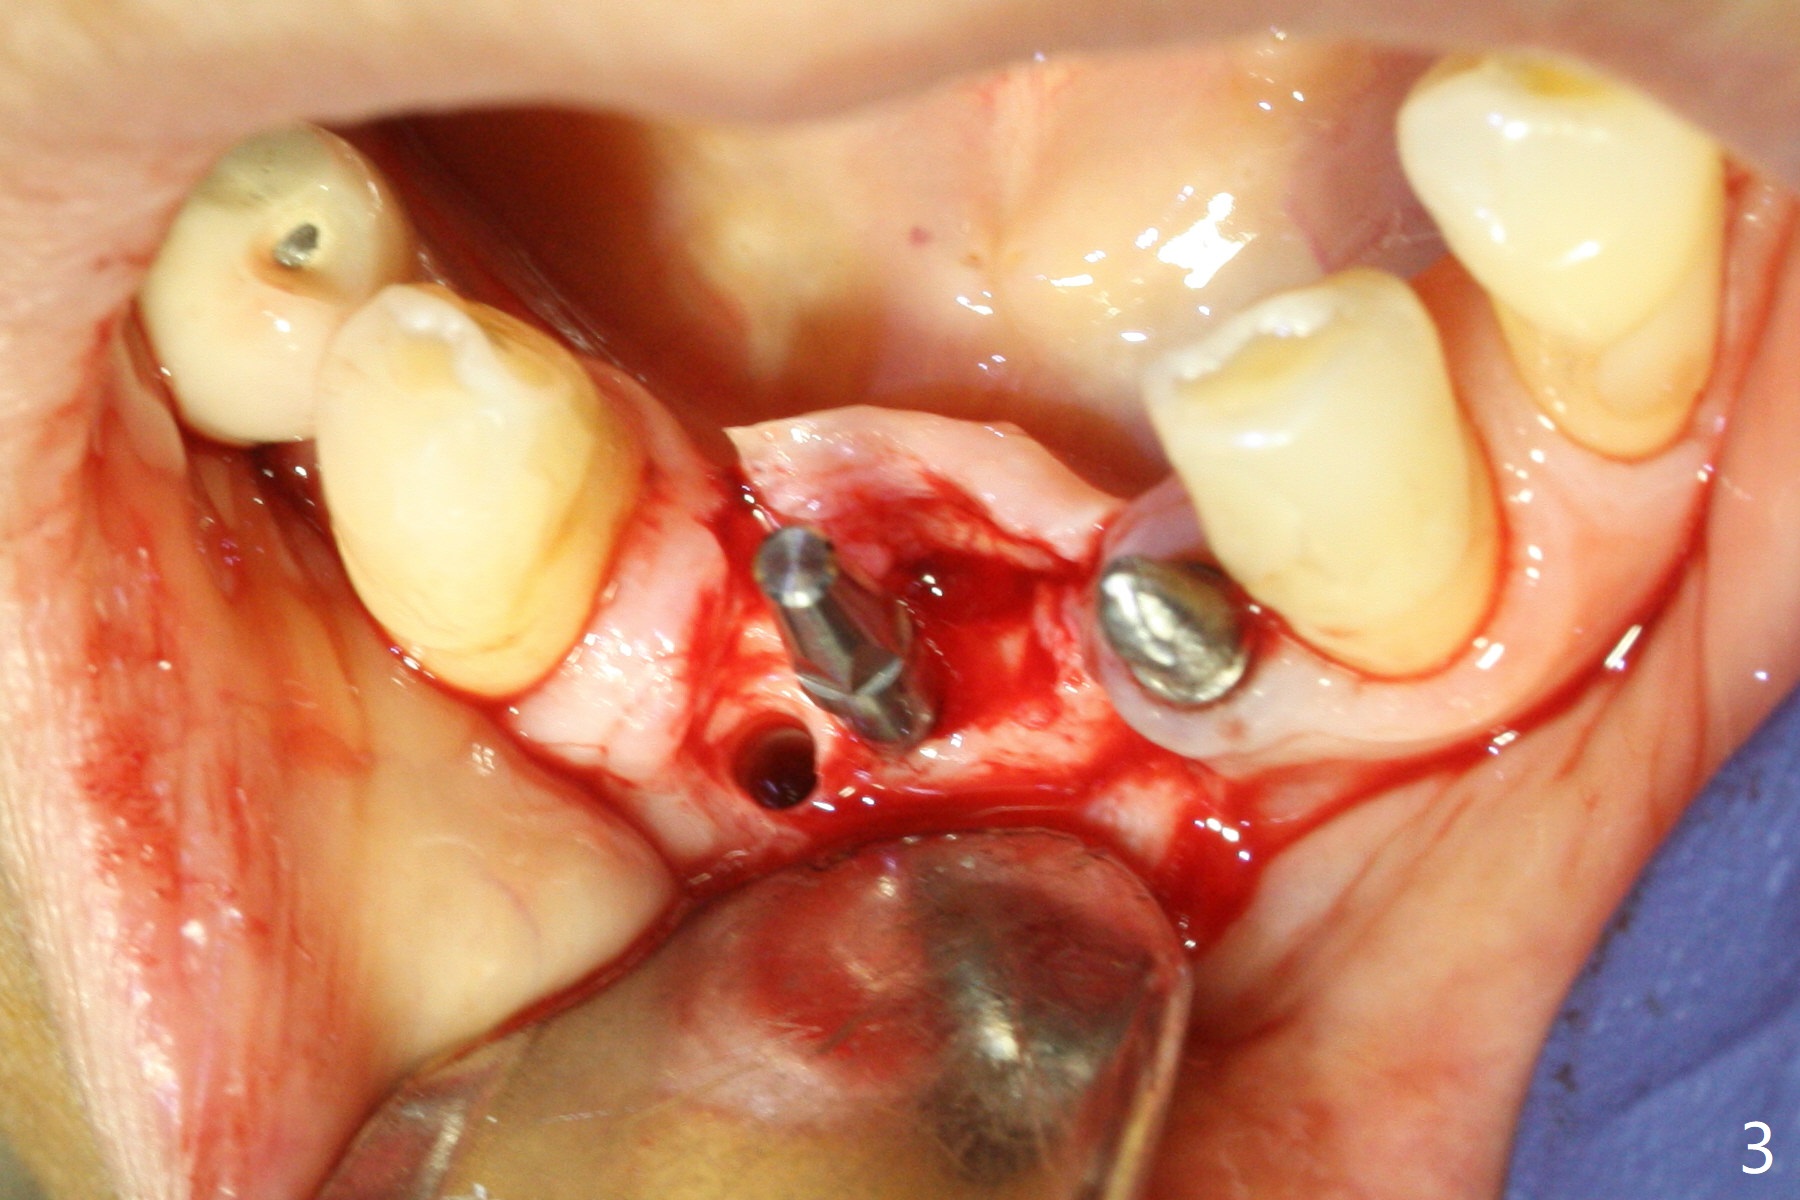

After removing #23-26 FPD and the 3x14 mm 1-piece implant at #26 (Fig.1,2 *), a new osteotomy is initiated in the narrow ridge (after ridge top reduction) approximately at #25 (Fig.2 <). Following placement a 2x10(4) mm implant at #25 (Fig.3-5) and Osteogen plug in the osteotomy at #26, Vanilla graft is placed around the implant, especially buccal. Periodontal dressing is applied after suturing. The buccal and lingual flaps are erythermatous and edematous without pain 8 days postop (Fig.6). The wound seems to be healing 2 weeks postop (Fig.7), no sign of osteonecrosis. With placement of a 2 mm implant at #25 (Fig.8 (>: bone graft buccally)), the buccal plate remains normal in thickness. When a 3 mm implant is placed at #23 (Fig.9), approximately 4 threads appear to be exposed (between arrowheads), partially due to the thick lingual plate (*).